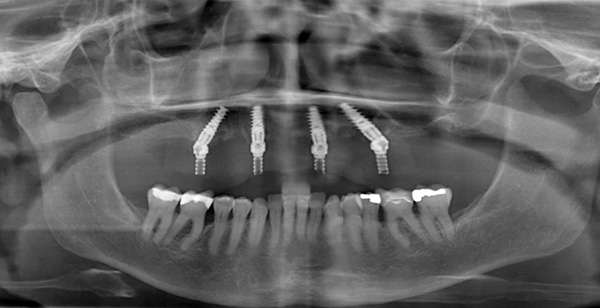

Установленные в верхнюю челюсть импланты

Суть данного вида протезирования заключается в установке 4х дентальных имплантов на одну челюсть, на которые уже крепится несъемный протез. Два из четыре имплантов устанавливаются во фронтальном (переднем) отделе костной ткани, а два оставшиеся в боковом или дистальном отделе и устанавливаются под углом 45°. Дистальный отдел - это задняя область в которой находятся коренные зубы «моляры» по 3 зуба с каждой стороны челюсти. При таком методе нагрузка от несъёмного протеза распределяется равномерно по челюсти и не вызывает осложнений в последствии.

Для фиксации протеза на имплантатах установленных в дистальном отделе под углом используется специальный наклонный мультиюнит-абатмент. Такая особенная конструкция позволяет крепить протез на импланте под 45 градусов с очень высокой степенью надежности.